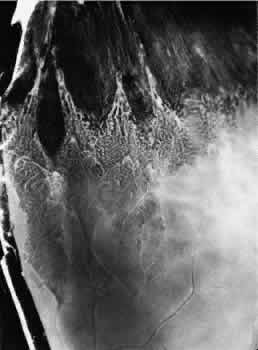

TYPICAL CYSTOID DEGENERATION

The most common form of degeneration of the peripheral retina is typical cystoid degeneration. Spaces develop in the outer plexiform and inner nuclear layers and coalesce to form interlacing tunnels; they are separated by pillars that extend from the inner to the outer retinal layers, giving the inner surface a uniformly stippled appearance (Fig. 15). The stippled depressions correspond to retinal pillars; the intervening rounded domes result from the intraretinal cystoid spaces.9 Degeneration begins at the ora serrata, particularly at the base of dentate processes, and extends posteriorly and circumferentially to form a band that may encircle the eye and reach from the ora serrata to the equator (Fig. 16).

Fig. 16. Typical and reticular cystoid degeneration found immediately behind the ora serrata and about enclosed ora bay near cut edge of calotte. Posteriorly, note the conspicuous vascular pattern of degeneration (seen as gray background), finely stippled surface pattern, and angular free margins (related to limitation by surface vessels).

This degenerative process may be noted in infants at 1 year of age; it is always present in both eyes of patients over 8 years of age, usually increases in area with advancing age, and is most extensive in the superior and temporal quadrants (see Table 3).10,11